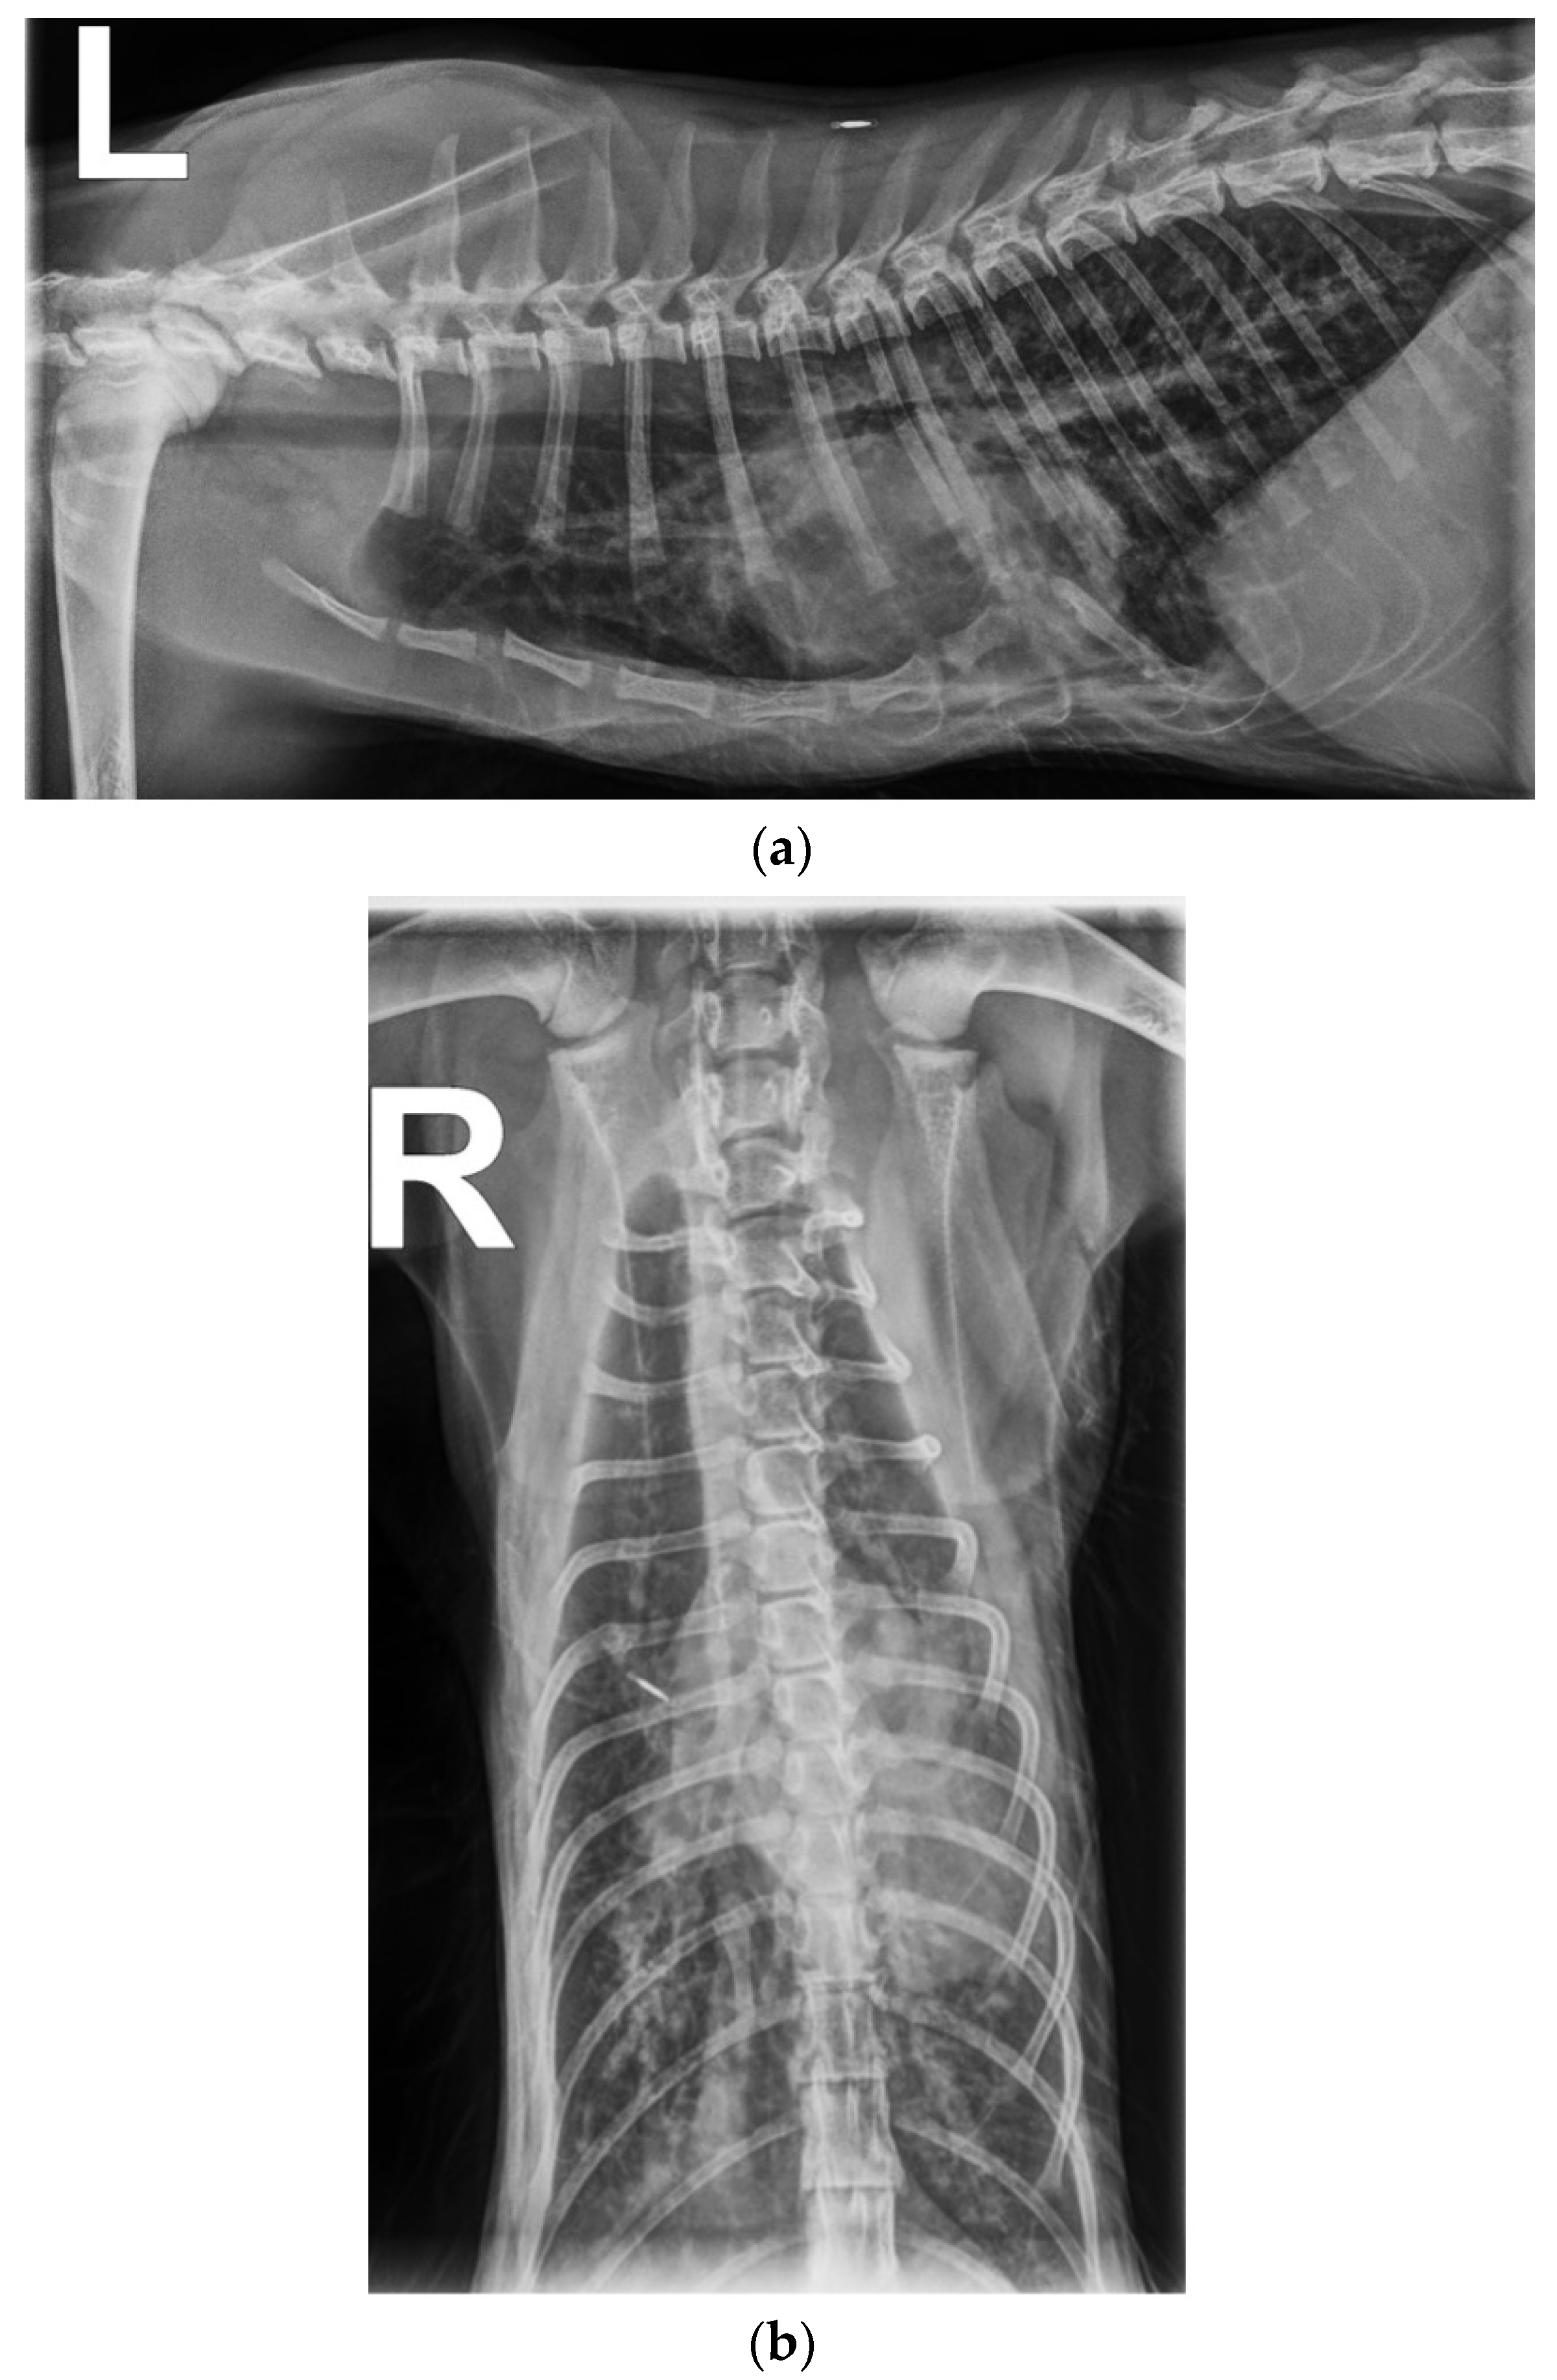

1. Case Description